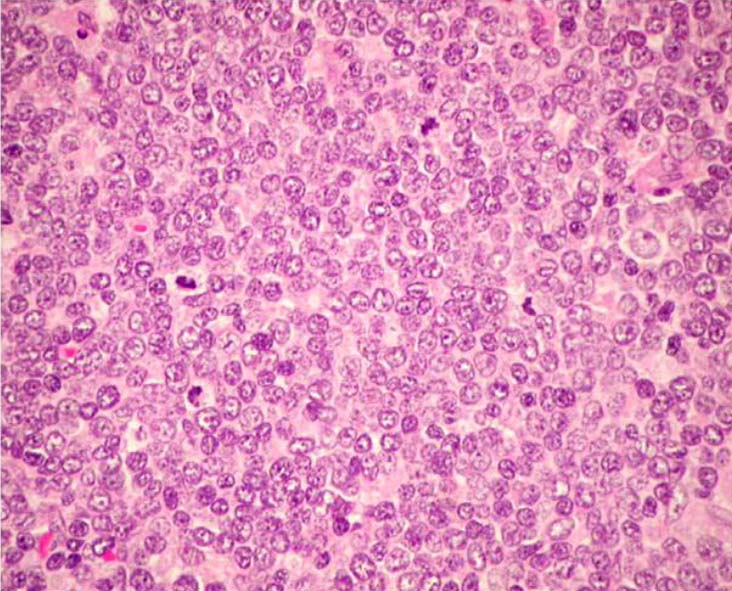

低倍率で見る増殖腫瘍細胞の単調さ, 均質さがきわだつことがMCLの診断に重要な所見である。均一な細胞の形態には, いろいろなヴァリエーションが見られる。

大きさの均一な小型ないし中型の細胞が増殖している。細胞質は乏しく, 不整で, でこぼこな(indented)核に中等度に粗いクロマチンが認められる。核小体は見えにくい。(核小体が明瞭なものはpleomorphic variantやMCL以外のリンパ腫を疑う。) 切れ込みのある核もしばしば出現する。小型円形核のリンパ球はT細胞で種々の程度に混在する。

Large cell(anaplastic centrocytic)/ blastic forms of MCL

MCLの20%に腫瘍細胞が通常のMCLより大きく, クロマチンはきめ細かく分散し, 小さな核小体が見られるhigh-grade variantが認められる。

2. blastoid variant

リンパ芽球型リンパ腫細胞のような繊細な核クロマチンでN/C比が高い類円形腫瘍細胞から成る。核分裂が多い。

3. pleomorphic variant

腫瘍細胞は脳回状にくびれた中ないし大型核をもつ。核小体も明瞭なものが出現する。核形態、細胞のサイズともに多形性に富む。HEではATLLなどのT細胞腫瘍やびまん性B細胞性リンパ腫の腫瘍細胞に似る。